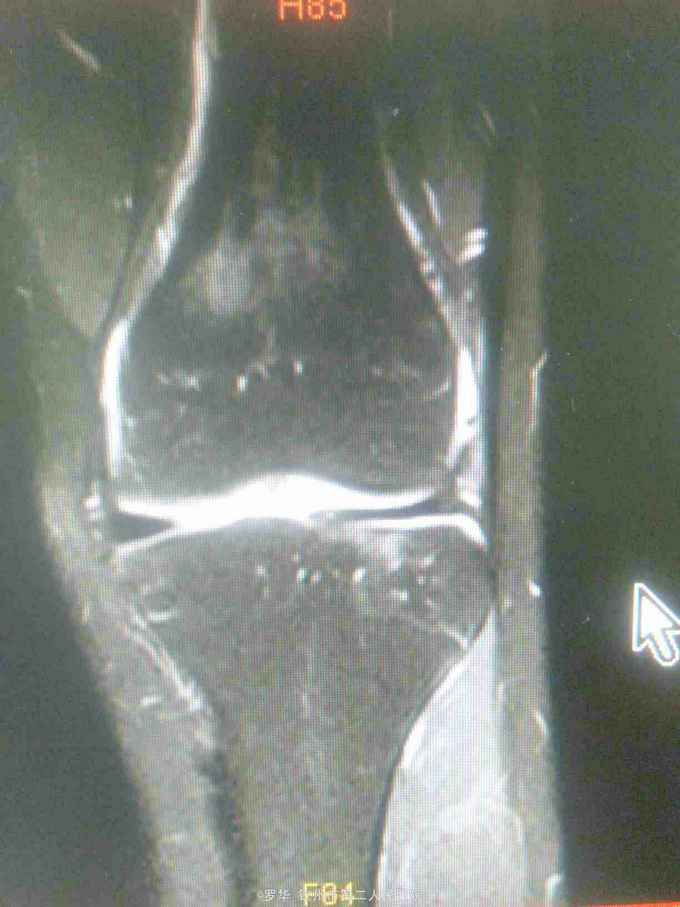

主诉:扭伤致左膝关节活动受限3月余。病史:患者男性,31岁,于入院3月余前扭伤左膝关节,致左膝关节肿痛、活动受限,尚可站立行走,但不能剧烈运动及重体力劳动,曾行磁共振检查提示左膝前交叉韧带损伤,半月板损伤,现为进上一步治疗入院。

查体:左膝关节无明显压痛,前抽屉试验阳性,侧方应力试验、麦氏征、研磨试验均阴性,膝关节屈伸活动可,余查体未见特殊。 辅查:膝关节磁共振提示左前交叉韧带损伤,左膝关节半月板损伤。

诊断:左膝关节前交叉韧带断裂,左膝关节半月板损伤。 治疗:予硬外麻下行左膝关节前交叉韧带重建术。